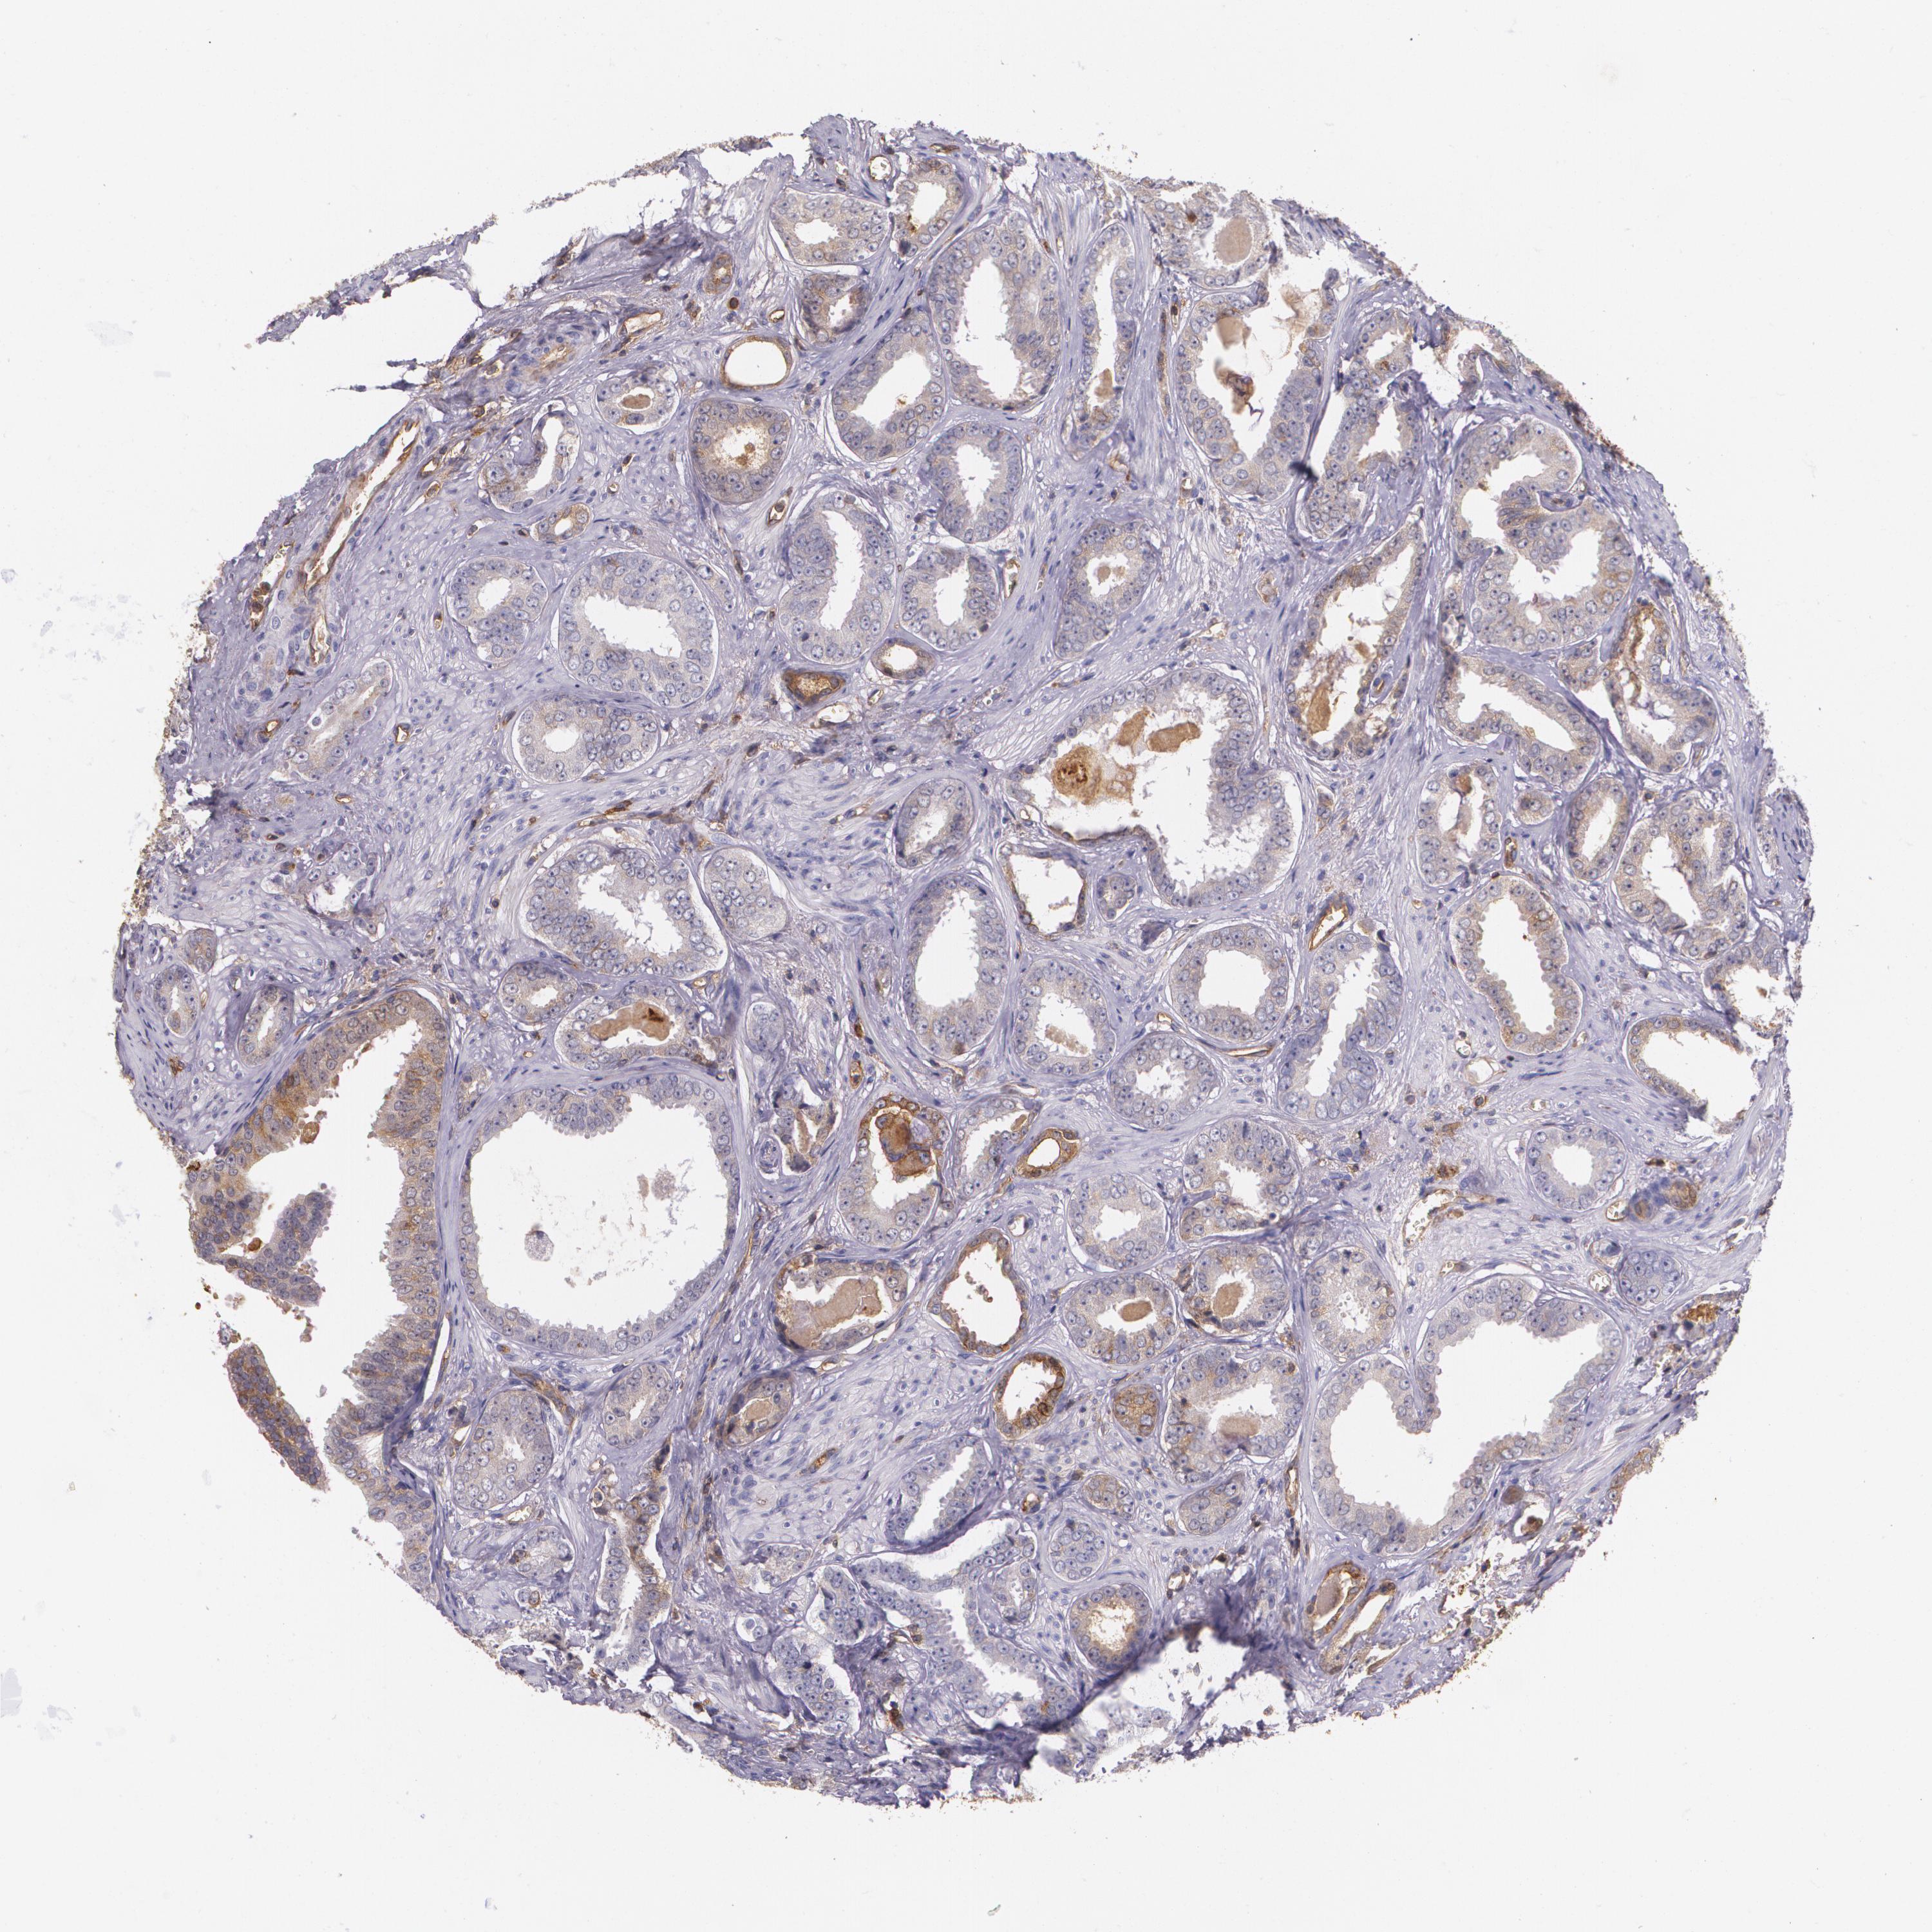

PROSTATE CANCER - Protein expressioni

A mouse-over function shows sample information and annotation data. Click on an image to view it in a full screen mode. Samples can be filtered based on level of antibody staining by selecting one or several of the following categories: high, medium, low and not detected. The assay and annotation is described here.

Note that samples used for immunohistochemistry by the Human Protein Atlas do not correspond to samples in the TCGA dataset.

Antibody stainingi

Antibody staining in the annotated cell types in the current human tissue is reported as not detected, low, medium, or high, based on conventional immunohistochemistry profiling in selected tissues. This score is based on the combination of the staining intensity and fraction of stained cells.

Each image is clickable and will lead to virtual microscopy that enables deeper exploration of all samples and also displays staining intensity scores, fraction scores and subcellular localization as well as patient and tissue information for each sample.

Antibody HPA006361

Antibody CAB002572

Staining

High

Medium

Low

Not detected

Intensity

Strong

Moderate

Weak

Negative

Quantity

>75%

75%-25%

<25%

None

Location

Nuclear

Cytoplasmic/membranous

Cytoplasmic/membranous,nuclear

Adenocarcinoma, Low grade

Adenocarcinoma, High grade

Adenocarcinoma, Medium grade